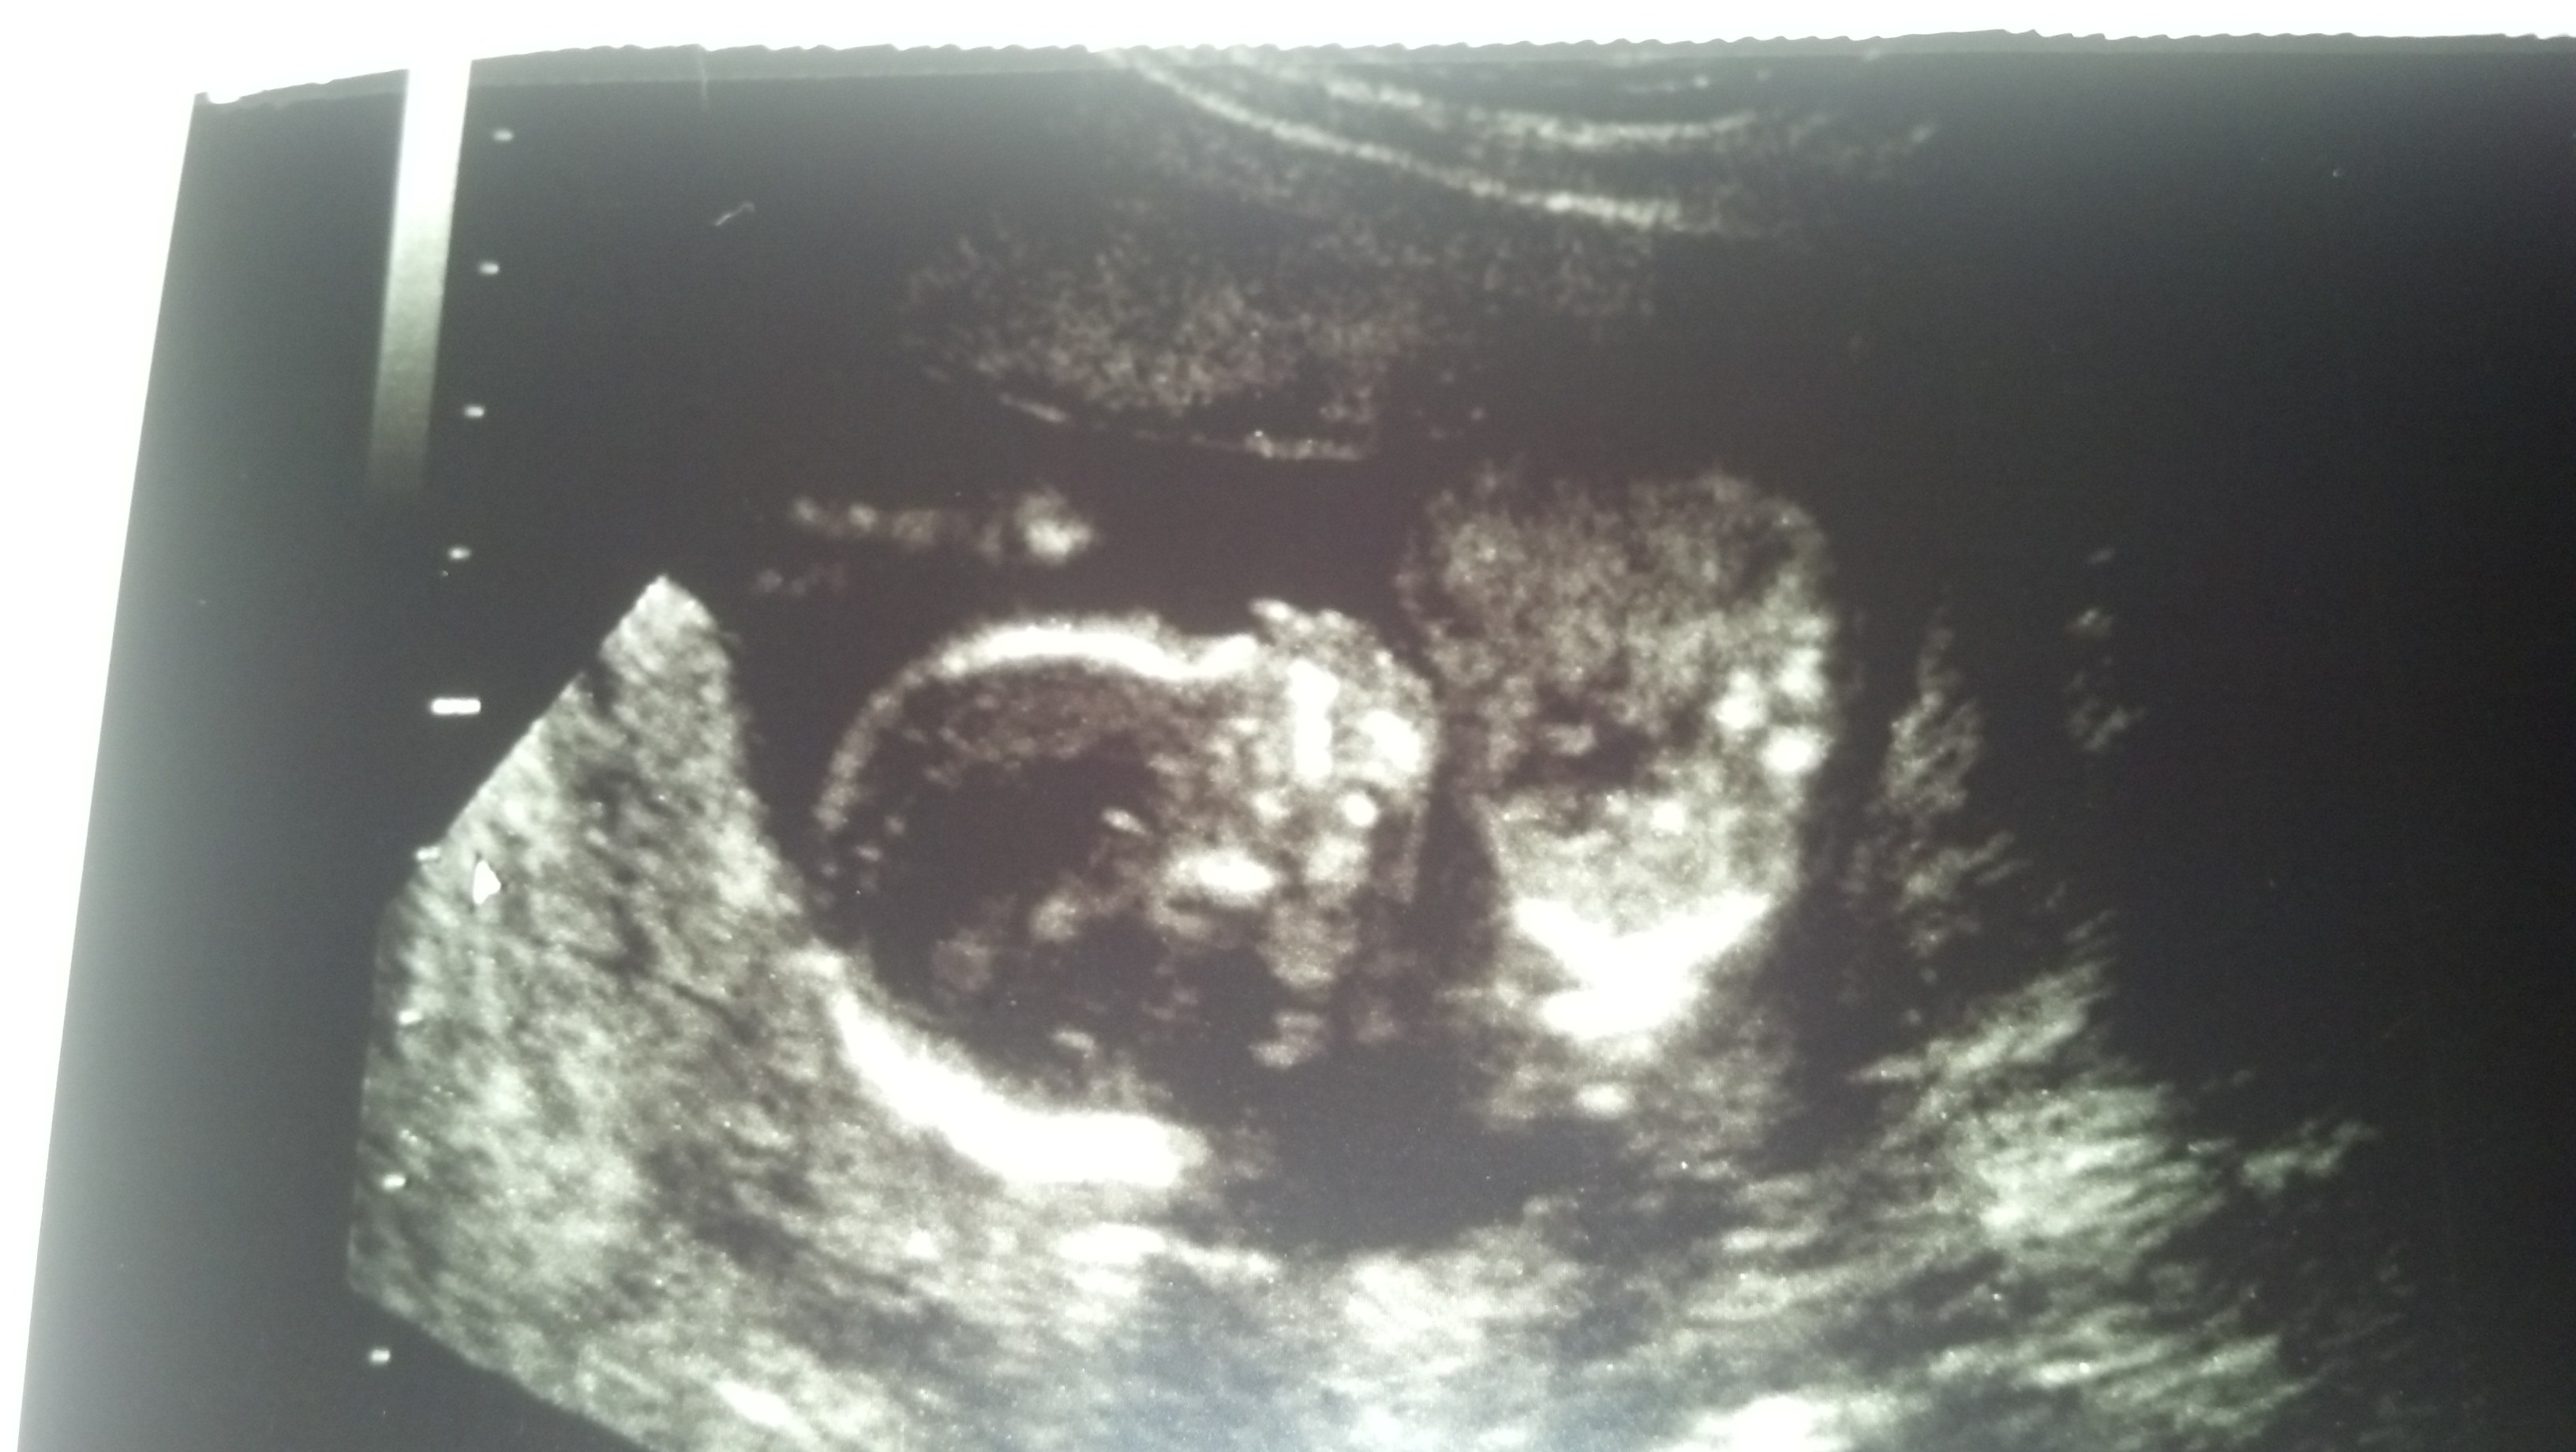

Attachment 14320Attachment 14321

yes did not expect it! i thought both my boys were girls and when i thought i was doomed for a 3rd boy i was extremely surprised still havent truely believed and prolly wont til she is born. I thought having a girl made you feel totally girly or something totally different from pregnancy with a boy.